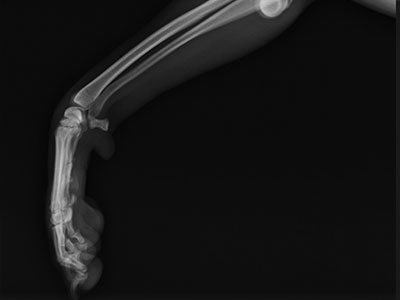

左前肢橈尺骨骨折

一個跳躍後左前肢突然不敢採地的壯壯,經X光確認為左前肢橈尺骨骨折,手術完美復位,目前已可正常行走。

術前